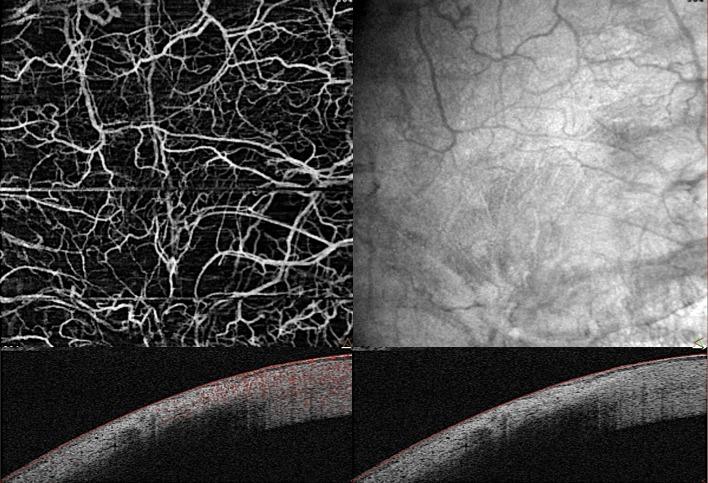

To evaluate the changes in conjunctival vascularization with optical coherence tomography angiography (OCT-A) before and after filtering surgery and to correlate these results with filtering surgery success.

Poor conjunctival vascularization was associated with lower IOP and a higher number of intraepithelial microcysts evaluated with OCT-A. OCT-A provides a simple, noninvasive, and reproducible method to analyze and quantify bleb vessels before and after filtering surgery.

Several studies have demonstrated that highly vascularized blebs might be associated with a higher risk of failure. OCT-A may provide a dye-free, noncontact method for monitoring conjunctival vascularization after filtering surgery.